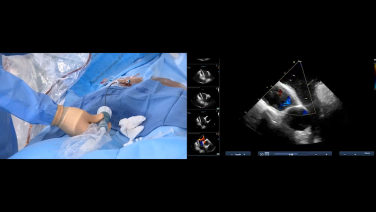

4D ICE for LAAO with Ashok Chaudhary, MD

Left Atrial Appendage Occlusion with NUVISION™ with Dr. Apoor Patel

Intracardiac Echo for Tricuspid, Mitral and LAAO - The NUVISION Experience